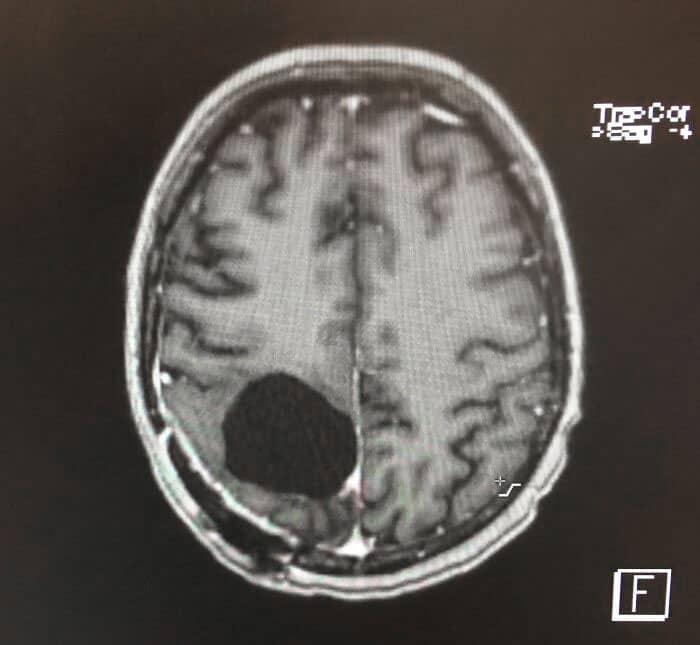

#2 I Had A Brain Tumor Removed, And Now I’m A Bit Absent Minded